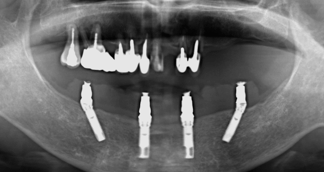

最低4本のインプラントを埋入し、それらを連結し、半日で固定式の仮歯まで入れて審美性、機能性を一日でとりもどせる革新的な治療。

1.従来インプラントは歯茎の中の骨に結合する3〜6ヶ月までは、歯をいれて噛ませることはできないと言われてきましたが、特殊な手術法によりインプラントを埋入し、4本〜6本を連結固定することにより、手術したその日からインプラントで食事を噛んでもらうことができるようになります。